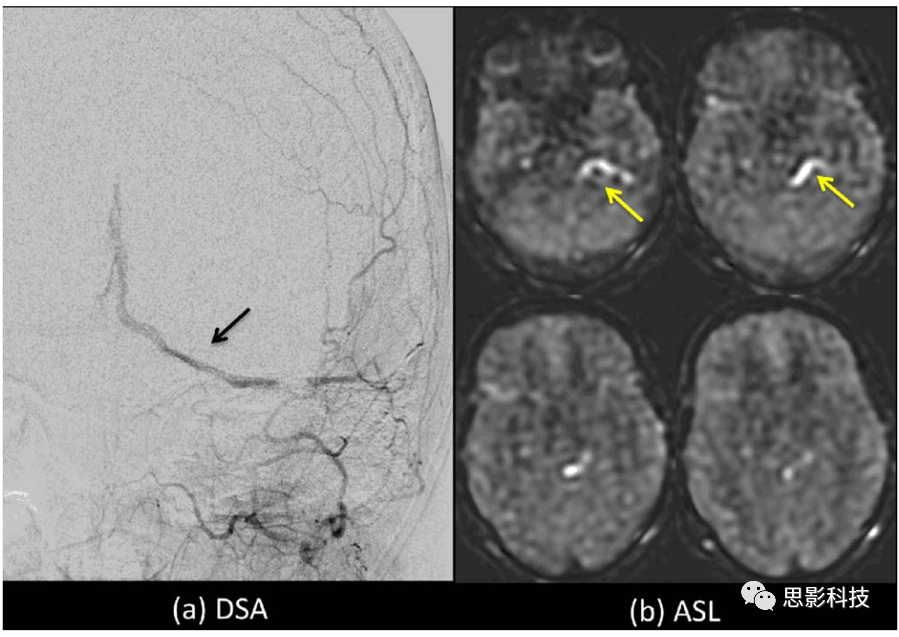

血流损毁梯度法

由于额外的梯度或T2准备模块的使用,在使用血流损毁梯度时可以有效地将TE延长,从而在asl图像中引入T2,会降低信噪比。在计算CBF时应该考虑到这一点。

在默认情况下,本文不鼓励使用血流损毁梯度,因为它们可能会损失更多重要的临床信息,例如延迟血流和动静脉分流等。对于单PLD成像,选择PLD应使其在大多数情况下比ATT长。这种情况下,标记的灌注血流将在成像之前输送到目标组织,并且在成像时未标记的血液会进入较大的动脉。在这种情况下,血流损毁梯度法对ASL图像的影响将最小。然而,当ATT>PLD时,ASL图像中会出现明亮的血管信号,这些信号会被去除。对于某些应用,例如在侧支血流中,明亮的血管信号的存在可能是一个有用的指标,表明存在长ATT的区域,并且这些区域量化的CBF值可能有误;此信息本身可能也具有诊断价值。在动静脉畸形中,识别静脉中的ASL信号在临床上也有实际意义。如图7所示。

Figure 7 DSA图像血管位置与ASL图像高信号区域吻合性的对比

本文建议将血流损毁梯度为用户控制的选项,因为它的使用有一定的限制条件。对于诸如在肿瘤中的应用,明亮的血管内信号可能掩盖了感兴趣的更细微的潜在的与灌注相关的信号。如果时间允许,两次有无血流损毁梯度的ASL扫描可能提供更有用的信息。这些选择与ASL最终在临床环境中最终使用的方式有关。鼓励研究人员去应用上述技术来多次尝试。

如前所述,对于多PLD /TI成像,ATT可以在CBF之外进行估计。如果没有血流损毁梯度,测量的ATT将表示标记的血流到达体素的时间,而如果有血流损毁梯度,测量的ATT将反映出微血管系统中的到达时间。这些不同的ATT在不同的应用中应该有不同的用途。如果没有使用血流损毁梯度,应该考虑血液内部流动的影响,否则计算出的CBF可能不正确。

关于使用血流损毁梯度的另一条注意点是,当灌注成像作为组分析的一部分进行时,由于在如大动脉等不规则位置存在高强度斑点,因此血管伪影会使分析变得复杂,在这种情况下,可以考虑选择一定的血流损毁梯度。

血流损毁的特征可用VENC描述,或者说是流速引起相移的速度。粗略地说,自旋在VENC上方消除相位影响,并在VENC下方保持可见。很高的VENC可以保留大动脉信号,而非常低的VENC可以延长ATT并降低信噪比。在使用时,建议以4cm/s的VENC在PC-AC方向上进行血流损毁梯度采集,这是一个很好的折衷方案。